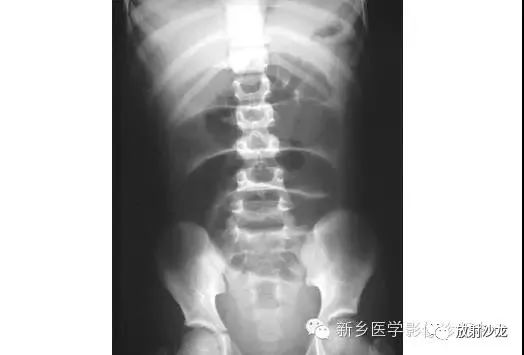

病例七:

上图为9岁,腹痛、呕吐患儿所做的腹部平片。该患儿有阑尾炎合并腹膜炎病史。影像学异常是什么,最有可能的病因是什么?腹部X线片显示小肠襻的明显扩张、环状襞的消失,这与小肠梗阻的诊断相一致。该患儿既往有腹膜炎病史,梗阻是由腹腔粘连造成的。这个孩子最终经保守治疗康复。